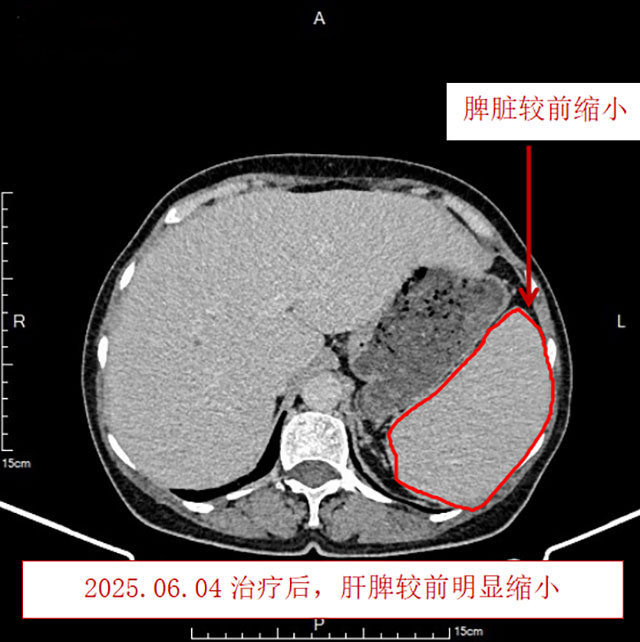

治疗后血小板恢复正常,心累、气促、乏力、汗多、潮热、双下肢水肿等症状均缓解,复查胸腹部CT发现淋巴结、肝脏、脾脏均较前明显缩小,复查骨髓未见异常B淋巴细胞。